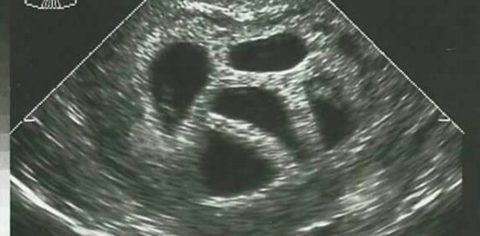

Margaret és Michael Baudinet 2011-ben házasodtak a Virginiai Egyetemen, és alig várták, hogy családot alapítsanak. Miután megtudták hogy babát várnak, sajnos hamar kiderült, hogy a magzat elvetélt, de úgy döntöttek, hogy nem adják fel. Újra meglátogatták az orvost, aki azt javasolta, hogy gyógyszerrel növeljék a termékenységi esélyüket. Nemsokára örömmel fogadták a hírt, hogy a teszteredmény pozitív. Boldogan indultak ultrahangra, ahol aztán megdöbbentette őket az orvos szava: Margaret legalább négy, de lehet, hogy ötös ikreket fogant.